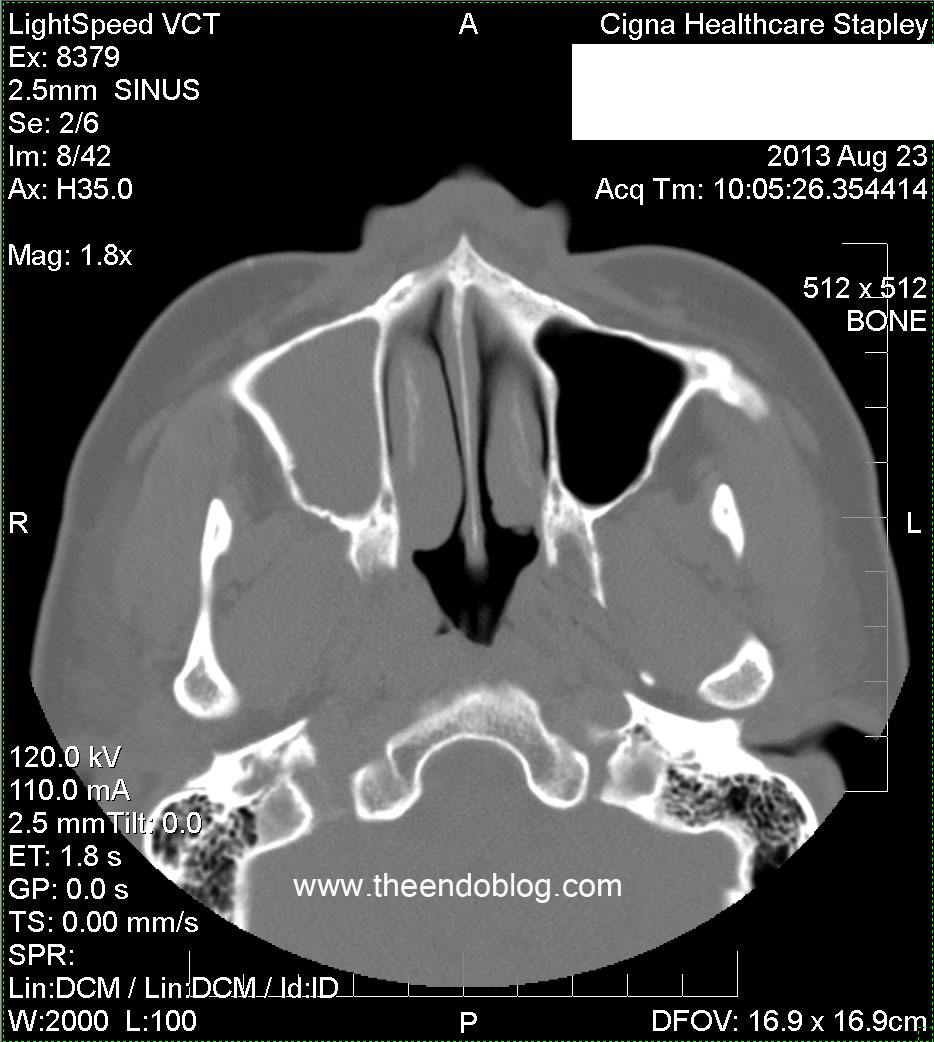

Complete opacification of the right frontal sinus.

Partial opacification of the R ethmoid sinuses.

Complete opacification of R maxilliary sinus, superior septal deviation to the right, bilateral opacified concha bullosas.

Molar #2 and #3 have periapical radiolucency (PARL), one of which is dehiscent into the maxillary sinus and buccal gingival sulcus.  This may be the most important diagnostic information in the CT scan.  Too often, radiologists and otolaryngologists are not looking at this part of the scan - if it is even included in the field of view.